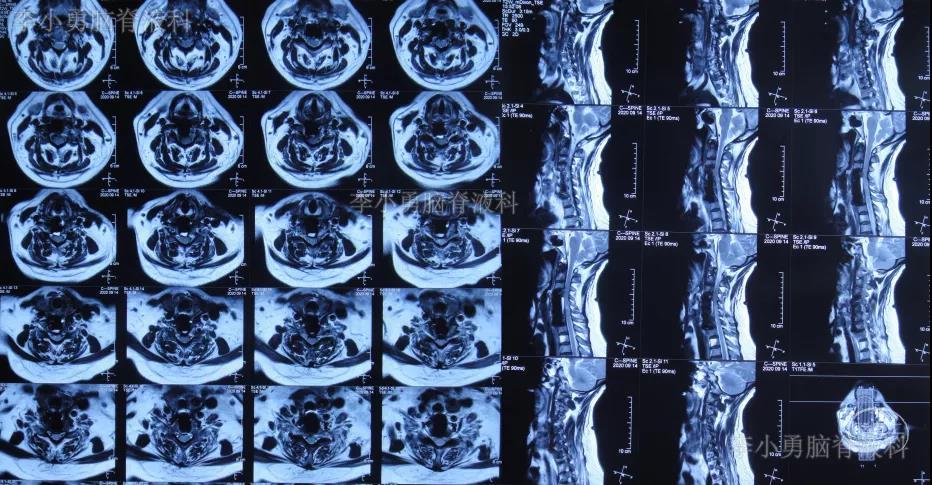

患者因间断性头晕、行走不稳,伴双上肢放射痛,麻木,于2020年4月11日入住北京某三级医院的中医骨伤科,当日查颈椎CT示椎管狭窄性颈椎病(图-1)。

图-1:2020年4月11日颈椎CT

图-2:2020年4月12日颈椎MR

2020年8月1日(即第一次颈椎病术后第101天)患者复查颈椎MR示颈椎病,椎管狭窄,颈髓受压(图-5)。

图-5:2020年8月1日颈椎MR

2020年8月13日(即第二次颈椎病术后第8天)患者开始出现颈部肿胀,床旁B超检查发现颈部切口深部积液,超声引导下穿刺抽出约87ml淡黄色透明液体,同时积液送细菌培养。2020年8月14日(即第二次颈椎病术后第9天)再次在床旁B超引导下穿刺抽液,抽出约90ml淡黄色透明液体,并加压包扎。复查颈部MR示术区皮下大量包裹性积液,考虑脑脊液漏(图-8)。

图-8:2020年8月14日颈部MR

2020年9月2日(入脑脊液科次日,即颈椎脑脊液漏修补术后第6天,即第二次颈椎病术后第25天)复查颈部MR示术区皮下深部仍有包裹性积液(图-10)。

图-10:2020年9月2日颈部MR